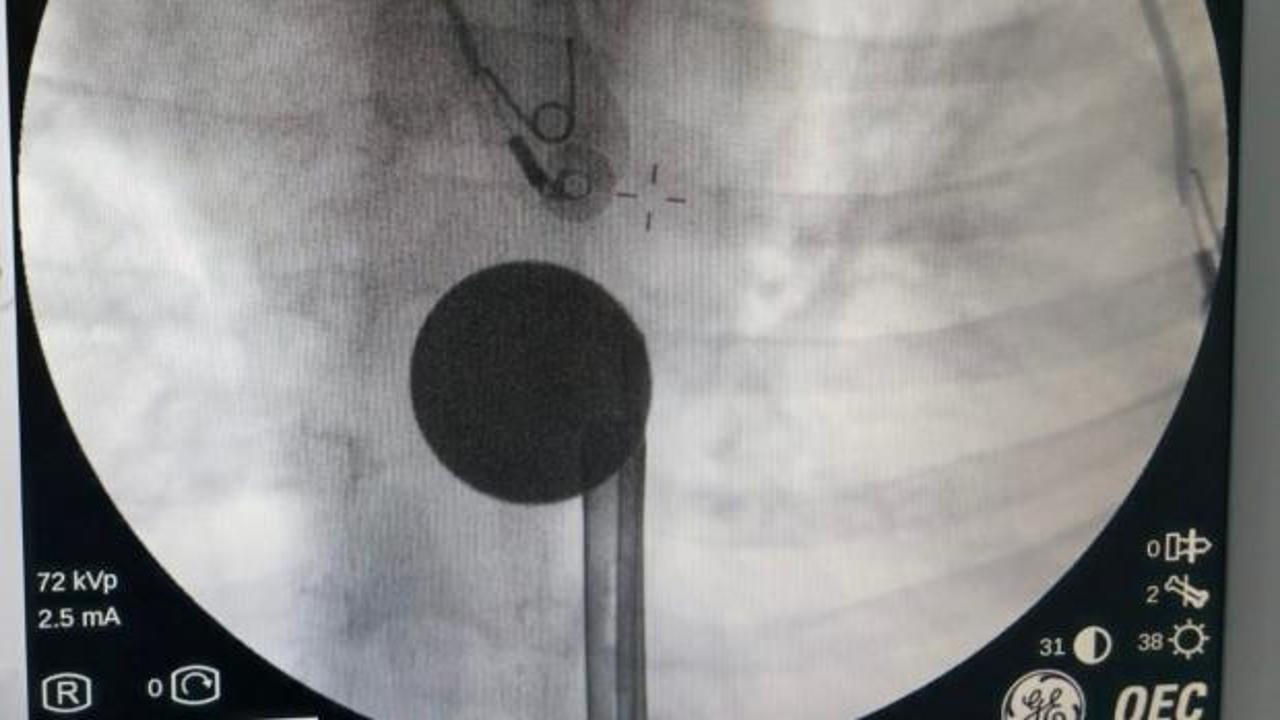

Paylaşılan bilgilere göre 8 yaşındaki Y.K., yabancı cisim yutma şikayetiyle ailesi tarafından Siirt Eğitim ve Araştırma Hastanesine götürüldü.

Yapılan ilk değerlendirme ve görüntüleme tetkiklerinin ardından çocuk, ilgili branşlar tarafından operasyona alındı.

Y.K.'nın yemek borusuna kadar ilerlediği tespit edilen madeni para, gastroenteroloji uzmanı Dr. Yaren Dirik ve kulak burun boğaz hekimi Yasin Gökçınar tarafından müdahale edilerek çıkartıldı.

Operasyonun ardından bir süre gözlem altında tutulan Y.K., tedavisinin tamamlanmasıyla taburcu edildi.

"Hastanemize başvuran 8 yaşındaki hastamızın yemek borusuna kaçan madeni para, gastroenteroloji ve KBB ekiplerimizin koordineli ve titiz çalışmasıyla herhangi bir komplikasyona yol açmadan başarılı bir şekilde çıkarılmıştır. Operasyon süreci sorunsuz geçmiş olup hastamızın genel durumu iyidir."